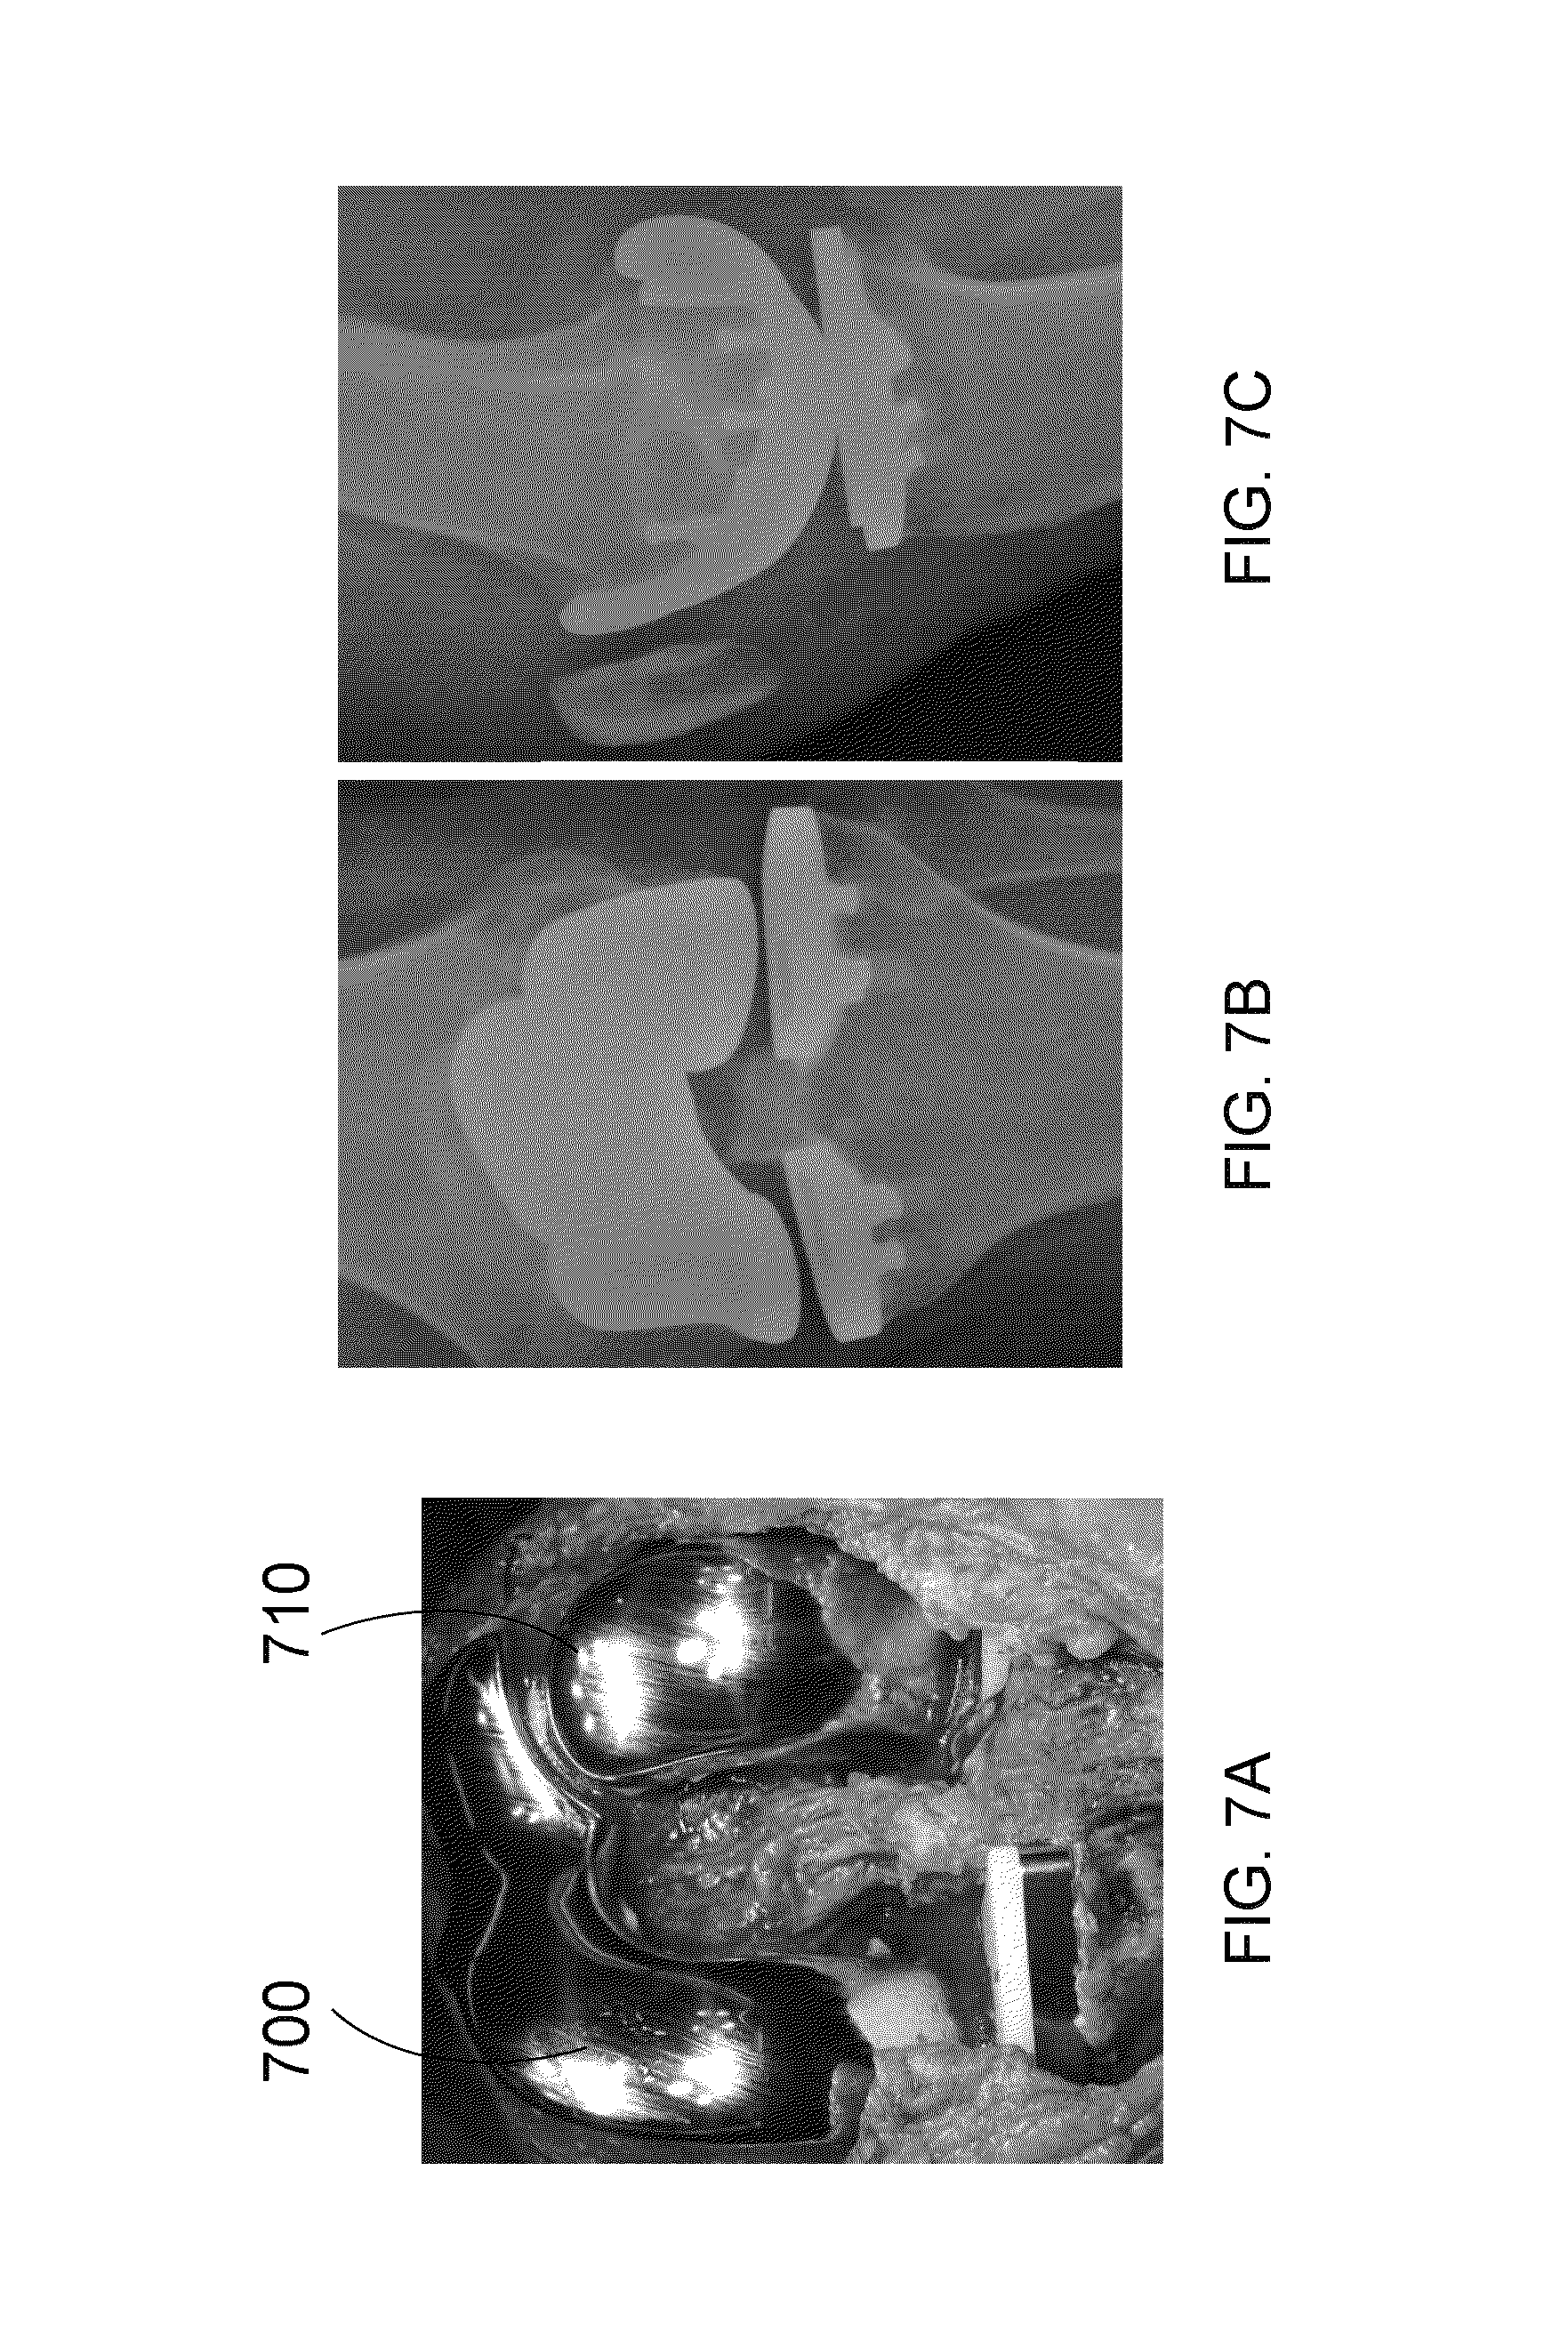

FIG. 7A is a photograph showing an exemplary knee replacement using a patient-specific bicompartmental device and a patient-specific unicompartmental device;

FIGS. 7B and 7C are x-ray images showing the device of FIG. 7A in the coronal plane and in the sagittal plane, respectively;